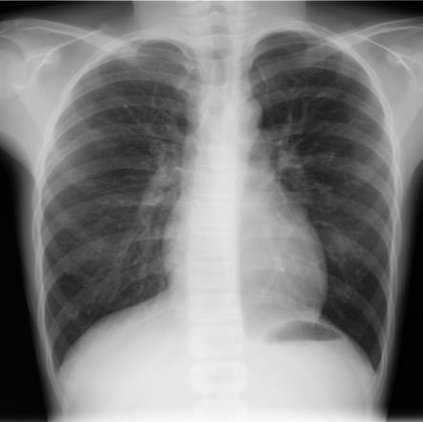

Tuberculosis (TB) remains a significant global health challenge, with pediatric cases posing a major concern. The World Health Organization (WHO) advocates for chest X-rays (CXRs) for TB screening. However, visual interpretation by radiologists can be subjective, time-consuming and prone to error, especially in pediatric TB. Artificial intelligence (AI)-driven computer-aided detection (CAD) tools, especially those utilizing deep learning, show promise in enhancing lung disease detection. However, challenges include data scarcity and lack of generalizability. In this context, we propose a novel self-supervised paradigm leveraging Vision Transformers (ViT) for improved TB detection in CXR, enabling zero-shot pediatric TB detection. We demonstrate improvements in TB detection performance ($\sim$12.7% and $\sim$13.4% top AUC/AUPR gains in adults and children, respectively) when conducting self-supervised pre-training when compared to fully-supervised (i.e., non pre-trained) ViT models, achieving top performances of 0.959 AUC and 0.962 AUPR in adult TB detection, and 0.697 AUC and 0.607 AUPR in zero-shot pediatric TB detection. As a result, this work demonstrates that self-supervised learning on adult CXRs effectively extends to challenging downstream tasks such as pediatric TB detection, where data are scarce.